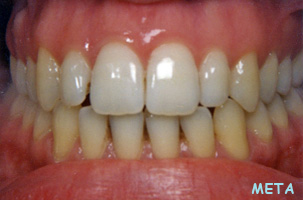

Η περιοδοντική νόσος μετακινεί τα δόντια καθώς το κόκαλο που τα υποστηρίζει υποχωρεί σταδιακά. Έτσι τα δόντια εμφανίζουν διαστήματα μεταξύ τους ή/και περιστρέφονται. Η ορθοδοντική θεραπεία επαναφέρει τα δόντια στις ορθές τους θέσεις και τέλος τα ακινητοποιεί ώστε να διασφαλιστεί η μακροβιότητά τους στο στόμα.